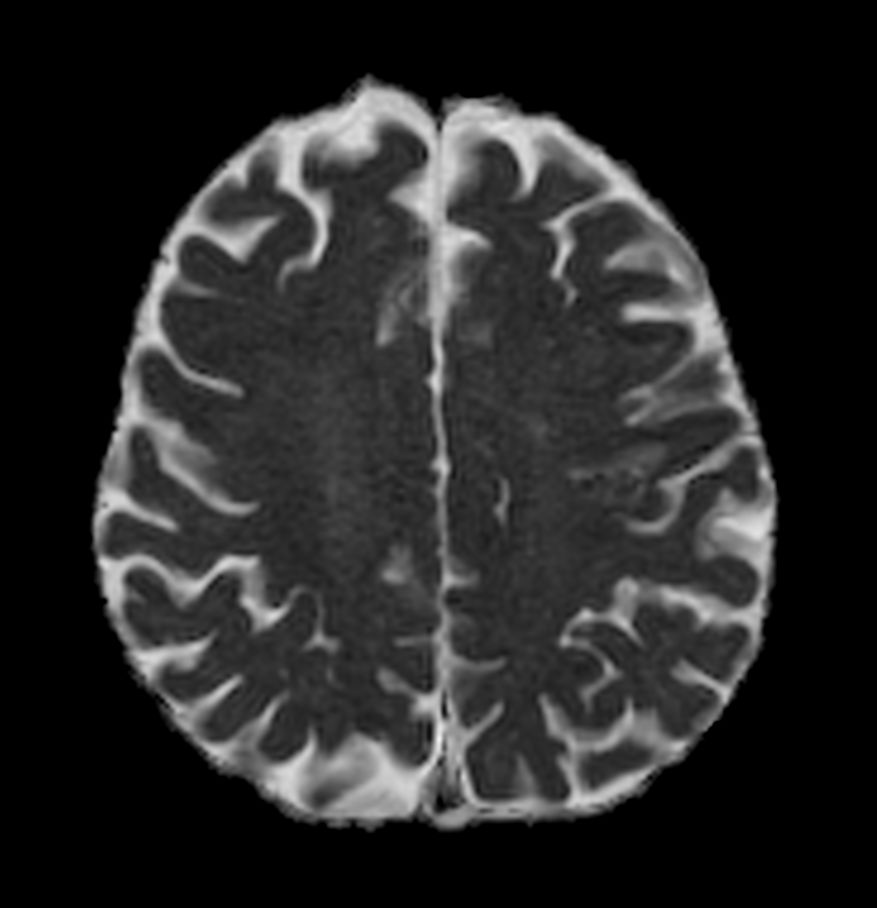

Patient with a small brain infarction. Compressed SENSE acceleration is used to speed up sequences while maintaining equal image quality. Three different diffusion methods are included; A fast 52 secs DWI EPI sequence, a high resolution DWI EPI sequence and a TSE based DWI sequence. A SWIp sequence is included offering high resolution 3D susceptibility weighted imaging to enhance contrast for deoxygenated (venous) blood or calcium deposits. 3D APT sequence is included providing contrast-free brain imaging, addressing the need for more confident diagnosis in brain neuro oncology by using the presence of endogenous cellular proteins to produce an MR signal. And a large FOV TOF MR Angiography sequence is included to check on brain vascular anatomy.

Axial DWI EPI (ADC)

Axial DWI EPI (ADC) - High resolution

Axial DWI TSE XD (ADC)